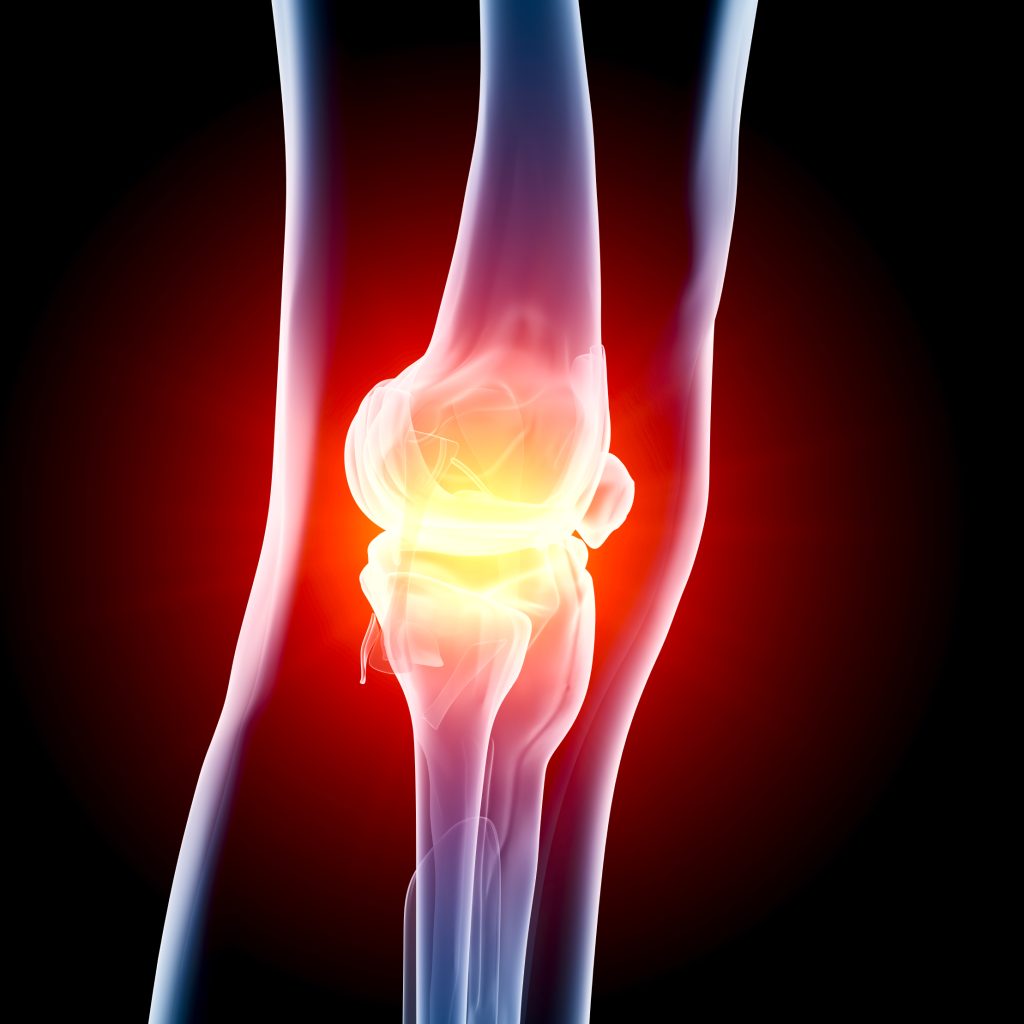

The knee is a mobile joint. The knee allows you to walk, climb, sit, kneel, and run. It also happens to be a common joint that wears and tears – either from sudden injuries, repetitive movement, age or arthritis.

The knee is a mobile joint. The knee allows you to walk, climb, sit, kneel, and run. It also happens to be a common joint that wears and tears – either from sudden injuries, repetitive movement, age or arthritis.